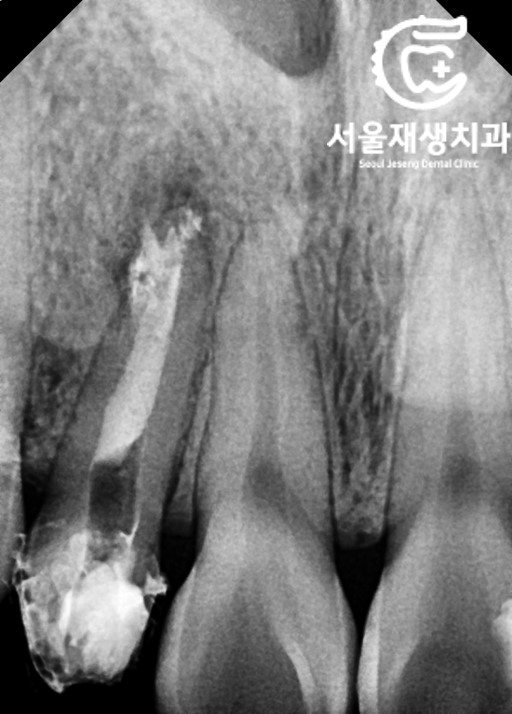

문제 치아를 확대해서 촬영하기

![[재신경치료] 소중한 내 앞니...재신경치료로 다시 한 번 살려 쓸 수 있습니다. (서울재생치과, 현미경신경치료) 관련 이미지 5](https://pub-9f2bb3498faf4d1d8714b41df24753e3.r2.dev/content/clinics/archive/nqmm0udu86/naver_blog/honeybeevuvu/assets/by_hash/08d3d35af842647d42fc31181d4ae8e6885e55c801aba266af5032e20329ee55.jpg)

문제가 되는 치아를

단독으로 촬영해보았습니다.

염증의 크기가 결코 작지 않습니다.

가능하다면 재치료를 통해

염증상태를 해소하고,

보다 예쁜 크라운으로 마무리를

해보자고 설명드렸습니다.

(잇몸의 그림자도 해결해보고요)